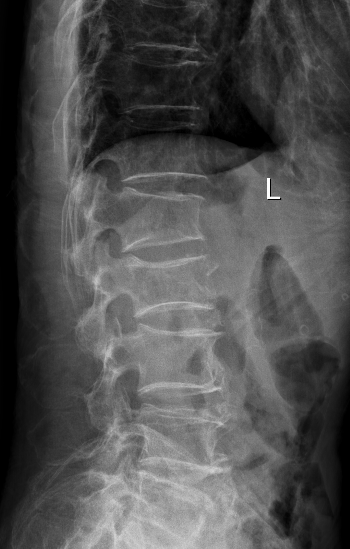

十余年来,我科室相继开展骨质疏松症的相关诊治工作,逐渐形成了自身的诊治体系,后经过整合联系,形成了以骨科二病区为龙头,联合检验科、放射科、内分泌科、血液风湿科等多学科结合、内外协作的骨松诊治MDT模式。目前采用的诊断方式有血钙及维生素ADKE检测、双能X线骨密度检测等,治疗方面也内外兼修,既可应用促成骨的四烯甲萘醌等,抑制骨吸收的唑来膦酸等药物治疗,又可采取椎体强化术、经皮穿刺椎弓根钉置入术等有效手术治疗,可结合患者自身情况,采取合适的治疗手段。开展骨质疏松诊治工作的十几年来,遵循指南,结合当地实际,总结归纳出了一套立足自身实际的诊疗体系,采取药物治疗与手术治疗相结合、因人而宜、综合施治的个体化的综合诊疗方案等。近年来,随着微创理念的推行和ERAS理念的实践,骨科二病区率先在本地区开创性的应用微创经椎间孔入路椎体强化术、经皮穿刺椎弓根钉置入术等先进治疗手段,实现立竿见影的治疗效果,深得广大患者的好评,取得了良好的社会效益和学术影响力,使桓台百姓足不出县即可享受到国内外先进的脊柱外科诊治体验。

术后术前